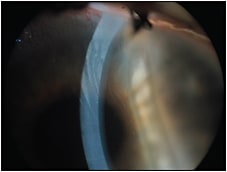

Beyond the epithelial defects, we observed stromal neovascularization (Figure 3) and an unstable tear film. There was also a mild, localized keratinization, probably due to the unstable tear film.

Figure 3. Stromal neovascularization.